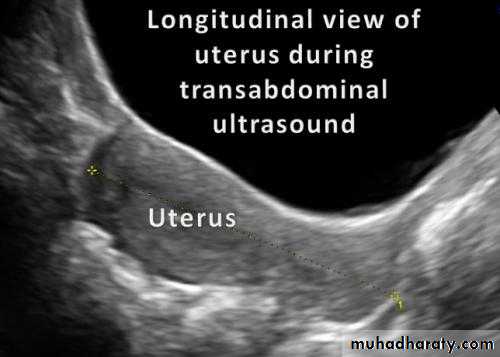

Normal Uterus

Normal Uterus in longitudinal view